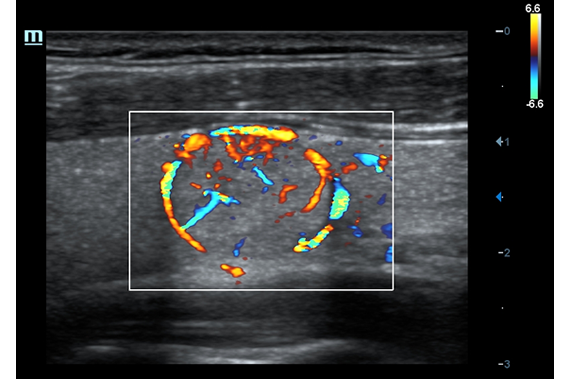

• HR Flow - режим отображения кровотока с высоким временным и пространственным разрешением для точной и однородной визуализации сосудов, в том числе самых мелких.

Энергетический допплер:

Цветовой допплер:

• HR Flow - режим отображения кровотока с высоким временным и пространственным разрешением для точной и однородной визуализации сосудов, в том числе самых мелких